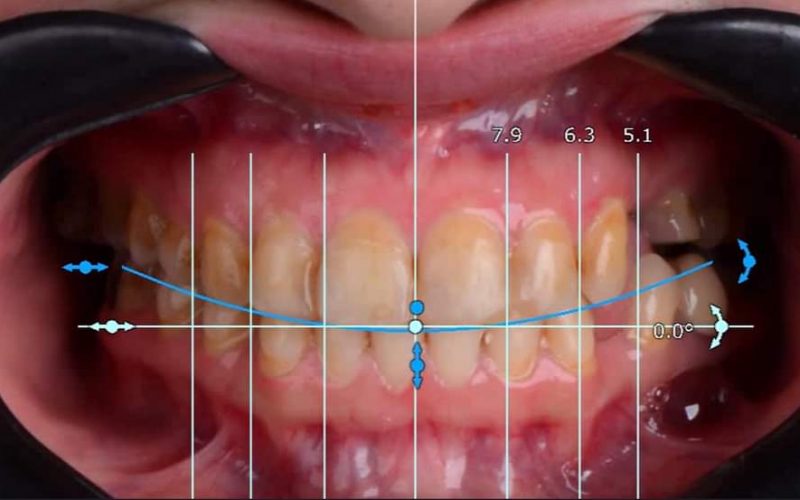

Gallery

Advanced Technology